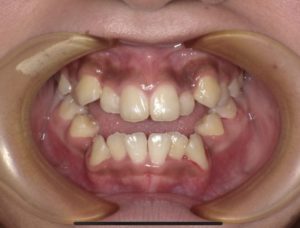

🦷検査時

この患者様は開咬で奥歯以外が全く嚙み合っていない状態です。

前歯で噛むことが出来ない為食事も大変ですね😞

舌癖の影響で開咬となっている為、MFT(口腔筋機能療法)がとても大切となります。